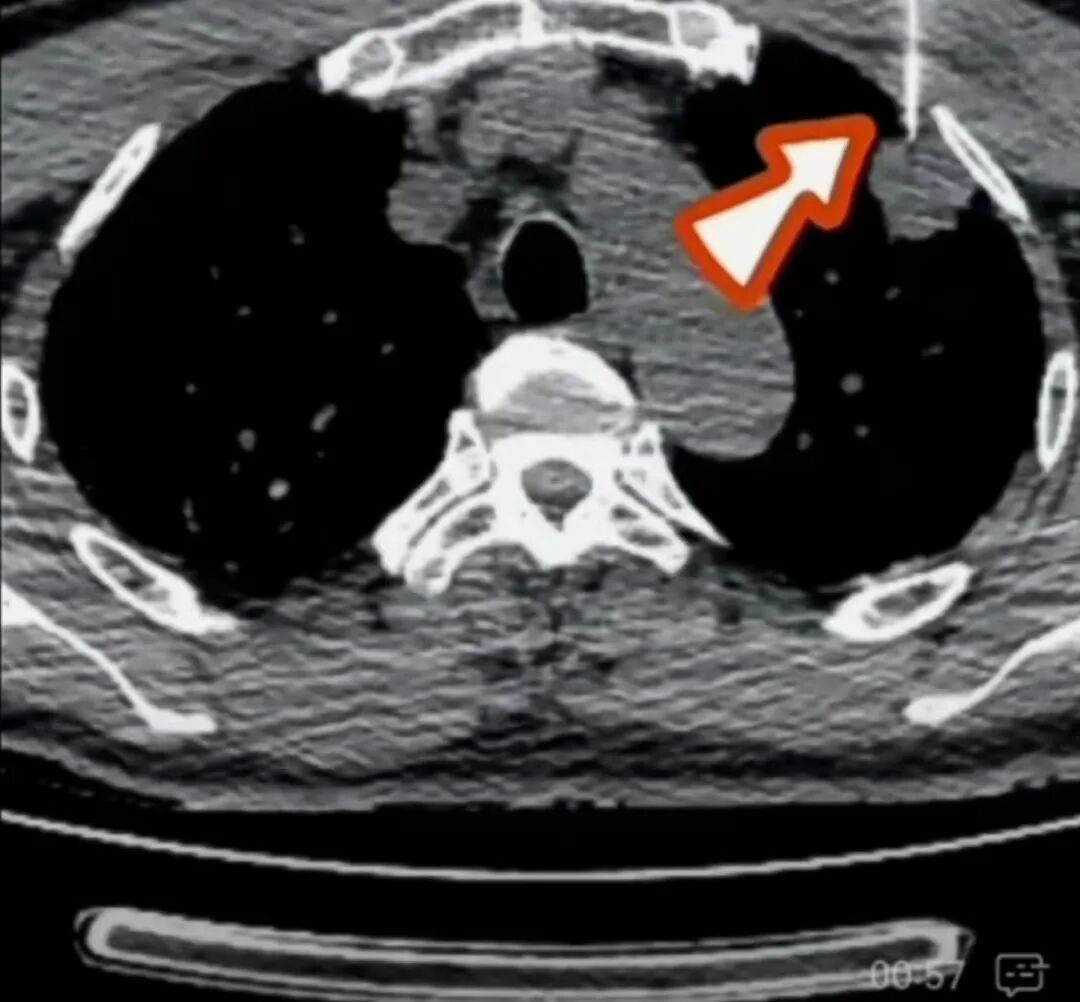

1、恶性肿瘤精准靶向治疗:肿瘤的分子靶向治疗是依据已知肿瘤发生中涉及的异常分子和基因,设计出针对这些特定分子和基因靶点的药物,通过药物干扰参与肿瘤细胞增殖分化所需要的分子,阻止肿瘤的生长和扩散。靶向治疗就像一颗颗精准发射的导弹,直击癌细胞;以肺癌为例,以前肺癌晚期平均生存时间只有10个月左右,现在通过靶向药治疗很多肺癌晚期患者生存期可以达到四五年实现长期生存。